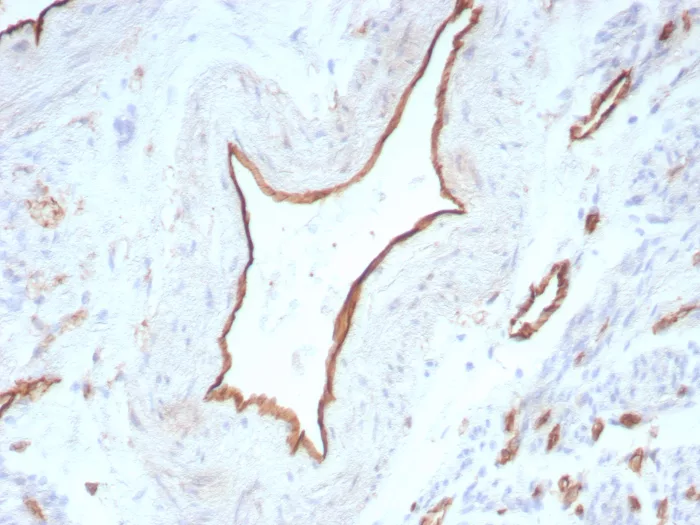

Formalin-fixed, paraffin-embedded human uterus stained with CD31 Rabbit Recombinant Monoclonal Antibody (C31/8831R). HIER: Tris/EDTA, pH9.0, 45min. 2°C: HRP-polymer, 30min. DAB, 5min.

CD31 (PECAM-1) is a transmembrane glycoprotein member of the immunoglobulin supergene family of adhesion molecules. CD31 is expressed by stem cells of the hematopoietic system and is primarily used to identify and concentrate these cells for experimental studies as well as for bone marrow transplantation. Anti-CD31 has shown to be highly specific and sensitive for vascular endothelial cells. Staining of nonvascular tumors (excluding hematopoietic neoplasms) is rare. CD31 MAb reacts with normal, benign, and malignant endothelial cells which make up blood vessel lining. The level of CD31 expression can help to determine the degree of tumor angiogenesis, and a high level of CD31 expression may imply a rapidly growing tumor and potentially a predictor of tumor recurrence.